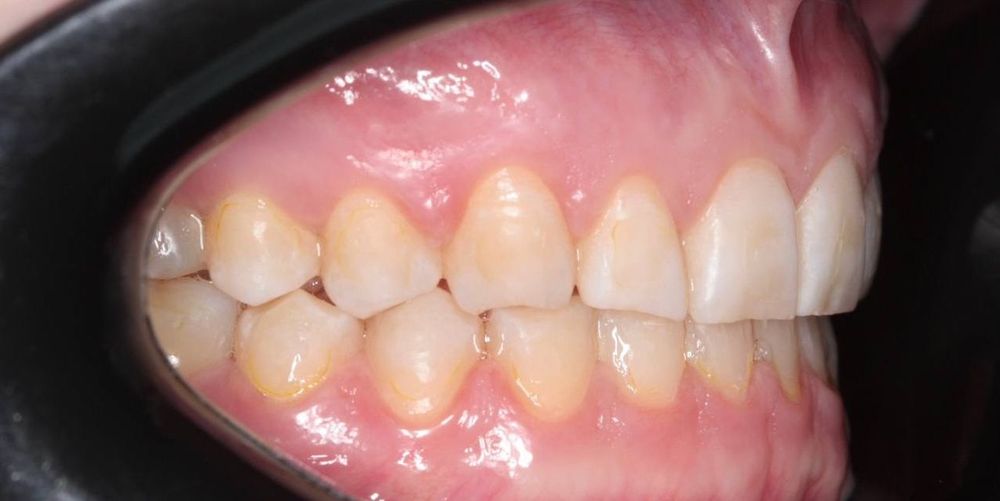

- глубокий прикус исправлен

- зубы выровнены, улыбка стала гармоничной и красивой

- восстановлено нормальное жевание и комфорт в суставе

- снижена стираемость эмали, улучшена функциональность всей зубочелюстной системы